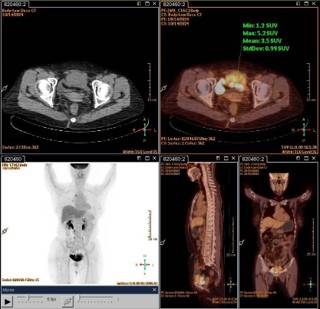

A 64-year-old woman presented with recurrent lower abdominal distension and discomfort for one week. After undergoing a pelvic CT scan, the results showed a lesion in the pelvis, a mass in front of the bladder, and it was considered to be a tumor with a high probability of malignancy (Figure 1A). The boundary between the lesion and the abdominal muscle on the front side was unclear, and there was a possibility of a vascular tumor thrombus on the left side (Figure 1B). There was a possibility of metastasis to multiple lymph nodes on the left side of the iliac external, obturator, and lateral branches of the aorta. In September 2024, due to the unclear nature of the lesion, we first performed a transurethral resection of the bladder lesion under general anesthesia to establish a definitive diagnosis and alleviate the patient’s sensation of abdominal distension. The postoperative pathological results indicated that it was a malignant spindle cell tumor of the bladder. The results of postoperative immunohistochemistry showed: UP3 (-), Myogenin (-), MyoD1 (-), CK (-), VIM (+), SMA (partially +), KI-67 (approximately 60% +), GATA3 (-), DESMIN (-). Two weeks later, the patient experienced urethral bleeding after urination without any obvious predisposing cause, accompanied by mild low back pain. After a comprehensive PET-CT examination, the results indicated a space-occupying lesion on the anterior wall of the bladder with increased metabolism, suggesting a tumor. It has not involved the gastrointestinal tract and there is no evidence of distant metastasis (Figure 2). In October 2024, a robotic-assisted laparoscopic radical cystectomy + ileal conduit operation was performed under general anesthesia. Intraoperatively, we identified this neoplasm originating from the anterior wall of the bladder, which was adherent to the abdominal wall muscles (Figure 3A). The neoplasm was large in size, grotesquely shaped, and soft in texture, resembling a cord-like structure of the intestine. It had invaded the extra-bladder fat, and tumor thrombi were found within the lumens surrounding the bladder. Upon postoperative examination of the specimen, the bladder measured approximately 8.0 x 9.0 x 2.5 cm in size. A cord-like mass measuring about 7.0 x 5.0 x 3.0 cm was visible on the anterior wall of the bladder, with a gray-brown cut surface that was soft in texture (Figure 3B). Upon repeat pathological analysis, the results unequivocally indicated that this is a malignant spindle cell tumor (Figure 3C). Immunohistochemistry indicated: CKH (-), CKL (-), EMA (-), CAM5.2 (-), VIM (+), SMA (+), CK5/6 (-), P40 (-), GATA-3 (-), Desmin (-), ALK (-), UP-3 (-), KI-67 20% (+), S-100 (-), CD34 (+), CD68 (+), ER (-), PR (-), SS18 (-), Calponin (-), MC (-), CR (-), WT-1 (-), CD10 (-), MDM-2 (-), CDK4 (-), CD117 (+), DOG-1 weakly (+), Caldesmon weakly (+), STAT6 (-) (Figure 2B). Combined with the results of immunohistochemistry, the specimen was consistent with extra-gastrointestinal stromal tumor (the maximum diameter of the tumor is approximately 7 cm, the mitotic figure is about 3 per 50 high-power fields, high risk grade).

Figure 2: PET-CT scan indicates a localized, metabolically active space-occupying lesion in the anterior wall of the bladder, without involvement of the intestines and no evidence of distant metastasis